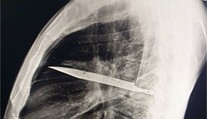

Zdravie Vykašliaval krv, vyšetrenie ukázalo poškodenie pľúc. Tínedžer fajčil elektronické cigarety od 12 rokov Lucia Tužáková 14. 2. 2025

Vapovala kvôli úzkosti. Teraz má 17-ročné dievča „popcornové pľúca“ a trvalé zdravotné následky Gabriela Šlebodová 20. 4. 2025